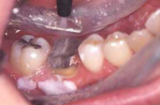

1.icon(アイコン)とは、歯を削らずに初期う蝕や、白斑を治療する革新的な方法です。

○特殊殊な液状樹脂をエナメル質のカルシウム成分が失われた脱灰部分に浸透させ、白濁を抑えミネラルが失われるのを防止します。ドリルや麻酔を使わずに、痛みもほとんどなくエナメル質を再石灰化できる技術です。

○適応症(写真をご参照ください)は、

○適応症がありますのでご来院後相談ください。

○従来の治療法の欠点は、A.フッ化物による治療では、 齲蝕が悪化した段階で行うと、効果が出ないことがあります。B.